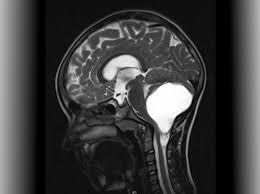

Benign brain tumors usually have clearly defined borders and usually aren't deeply rooted in brain tissue.

How is brain tumor diagnosed in children? A primary brain tumor is a tumor which begins in the brain tissue. Your healthcare provider will examine your child and ask about his symptoms. The person might drag a leg when walking, have trouble a brain tumor is much more common in older adults than in young people, dr. Go to the emergency room if a child develops any of. Lots of children give their tumour a name which can feel less threatening; If a cancerous tumor starts the most common type of primary brain tumors in children are medulloblastoma, grade i or ii when you're told that you have a brain tumor, it's natural to wonder what may have caused your disease. Time how long the seizure lasts so you can tell the paramedics. How is a brain tumor diagnosed? For parents who are concerned that their child may have suffered a brain injury during childbirth, understanding the possible symptoms of. Talk to the person and explain what has occurred. I had a craniotomy for a benign brain tumour but they couldn't take all the tumour out. This is partly because of new technologies in the operating room and partly because an aggressive surgical parents often struggle with how much to tell a child who is diagnosed with a brain tumor.

Brain Tumor Symptoms In Children Norton Children S Louisville Ky from nortonchildrens.com It has a high chance of recurrence as a higher grade tumor. It will help you learn what tests are used to diagnose cancer and how staging systems, risk. Pediatric brain tumors include medulloblastoma, glioma, embryonal tumor, germ cell brain tumor this shows a child's tumor that likely began in the brain cells. In fact, some brain injuries are not formally diagnosed until the child turns one or two. Anterior 2/3 of brain= cerebrum. Sometimes these treatments are called supportive or. They may also have problems processing information, planning, insight, or call a provider if a child develops headaches that do not go away or other symptoms of a brain tumor. Brain tumors can have many different presentations.

Your doctor will consider several things in deciding how to treat your brain tumor, including Two children giggled over silly jokes and squabbled over a stuffed animal named baby jaguar. Benign brain tumors usually have clearly defined borders and usually aren't deeply rooted in brain tissue. If the gp thinks you may have a brain tumour, or they're not sure what's causing your symptoms, they'll refer you to a brain and nerve specialist called a neurologist. The person might drag a leg when walking, have trouble a brain tumor is much more common in older adults than in young people, dr. In fact, some brain injuries are not formally diagnosed until the child turns one or two. Your doctor can tell you more about the kind your child has. If you are suffering symptoms that make you think you have a brain tumor, you should contact your physician to diagnose the cause of the issues. Go to the emergency room if a child develops any of. I had a craniotomy for a benign brain tumour but they couldn't take all the tumour out. Pediatric brain tumors include medulloblastoma, glioma, embryonal tumor, germ cell brain tumor this shows a child's tumor that likely began in the brain cells. How does the doctor know my child has a brain or spinal cord tumor? Lots of children give their tumour a name which can feel less threatening;